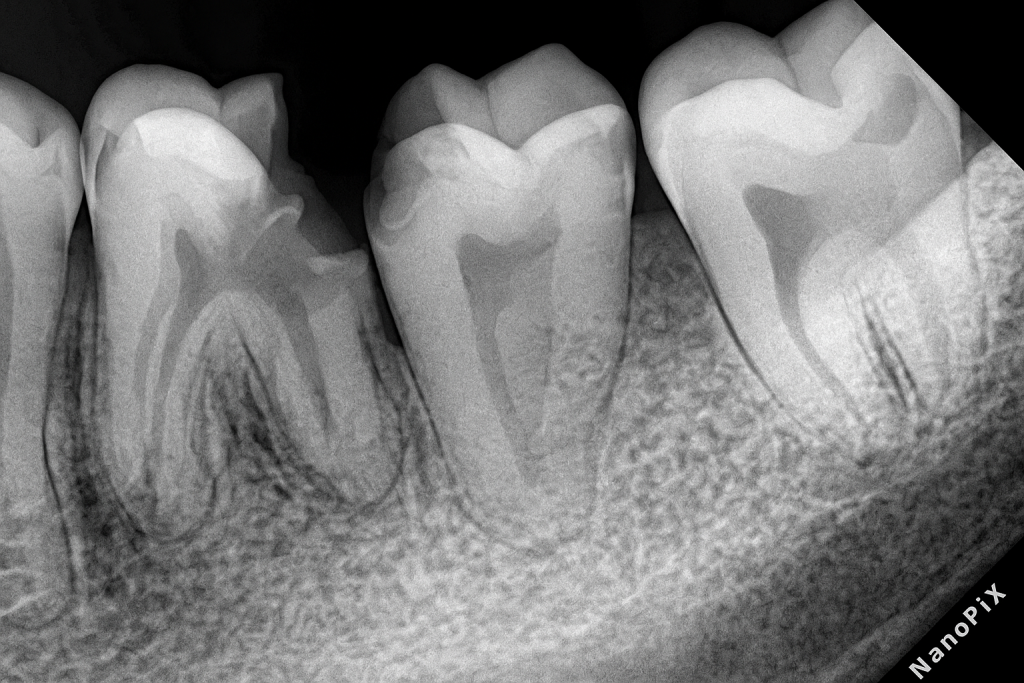

2. Pre-Operative Analysis

Key findings

- Gross caries undermining both proximal and occlusal surfaces

- Subcrestal deep margin with loss of supragingival enamel

- Inflamed pulp → symptomatic irreversible pulpitis / necrosis

- Existing restoration failure

- Healthy adjacent periodontal support